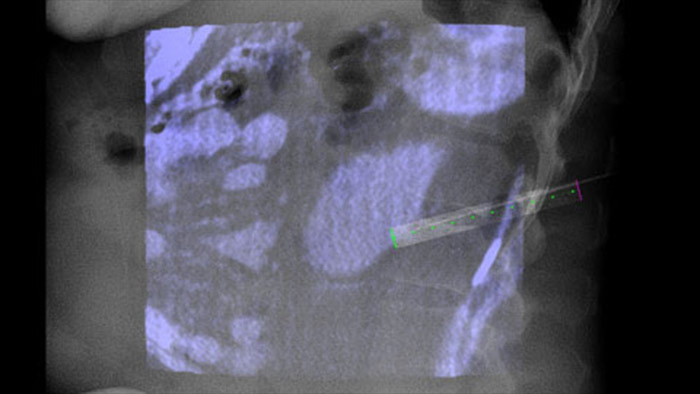

XperGuide provides highly accurate live image guidance of each needle to a targeted position by overlaying pre-planned trajectories with fluoroscopic imaging.3

With CBCT acquire a post-ablation CBCT to demonstrate the extent of tumor coverage and confirm completeness of your treatment.